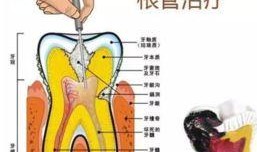

根管治疗视频,从视频学习根管治疗技巧与流程

最近牙疼得我简直要抓狂了!你知道那种感觉吗?就像有一颗小钢珠在你的牙髓里不停地滚动,痛得你连呼吸都小心翼翼。于是,我决定上网搜一...